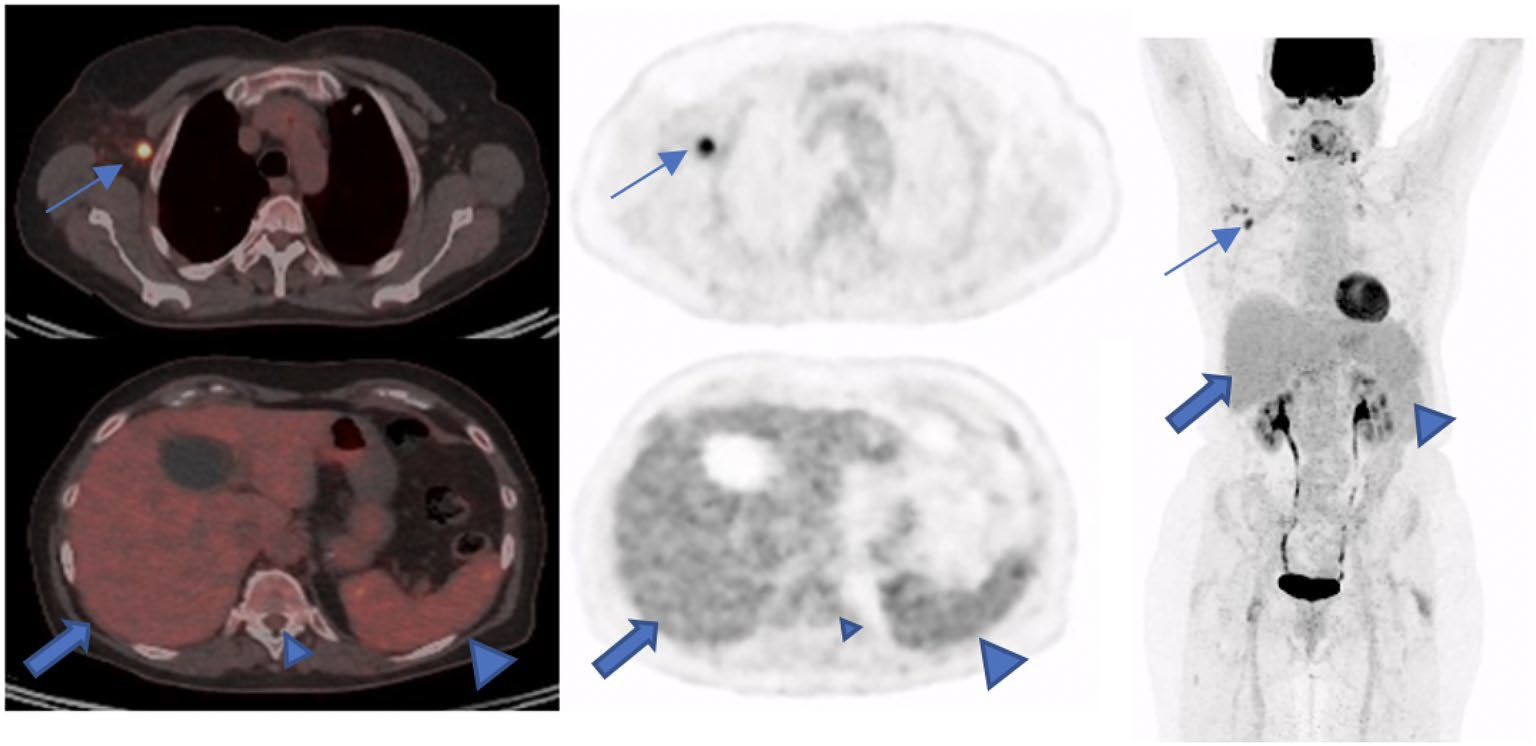

In a study in 20 healthy volunteers, the researchers found that a portable PET scanner measured brain metabolism based on F-18 FDG radiotracer uptake similarly to that of a standard PET scanner (Biograph mCT, Siemens Healthineers).

Each of the 20 healthy volunteers underwent dynamic F-18 FDG imaging with both scanners one to 154 days apart. Standard radiotracer uptake values (SUV) in brain tissue and rates of glucose metabolism (CMRglu) were quantified and compared between the scanners at regional and voxel levels.

According to the findings, outcome measures were well correlated, the group wrote. Specifically, correlation coefficients between the imaging sets across participants were 0.83 ± 0.07 for SUV and 0.85 ± 0.08 for CMRglu, the researchers reported.

“Our results indicate robust correlation and agreement between semi- and fully quantitative brain glucose metabolism measurements from portable CerePET and standard Biograph mCT scanners,” the group wrote.

Ultimately, at this stage, the major finding is that there appears to be no significant differences in fully quantified dynamic outcomes in cortical and subcortical brain areas between the two scanners indicating that the CerePET scanner is ready for imaging human subjects, they wrote.